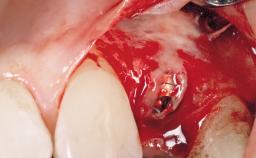

Early Placement of an Implant in a Maxillary Right Central Incisor Site

| Bone Augmentation | Horizontal|Simultaneous |

| Augmentation Materials | Autogenous chips|Xenogenous|Membrane |